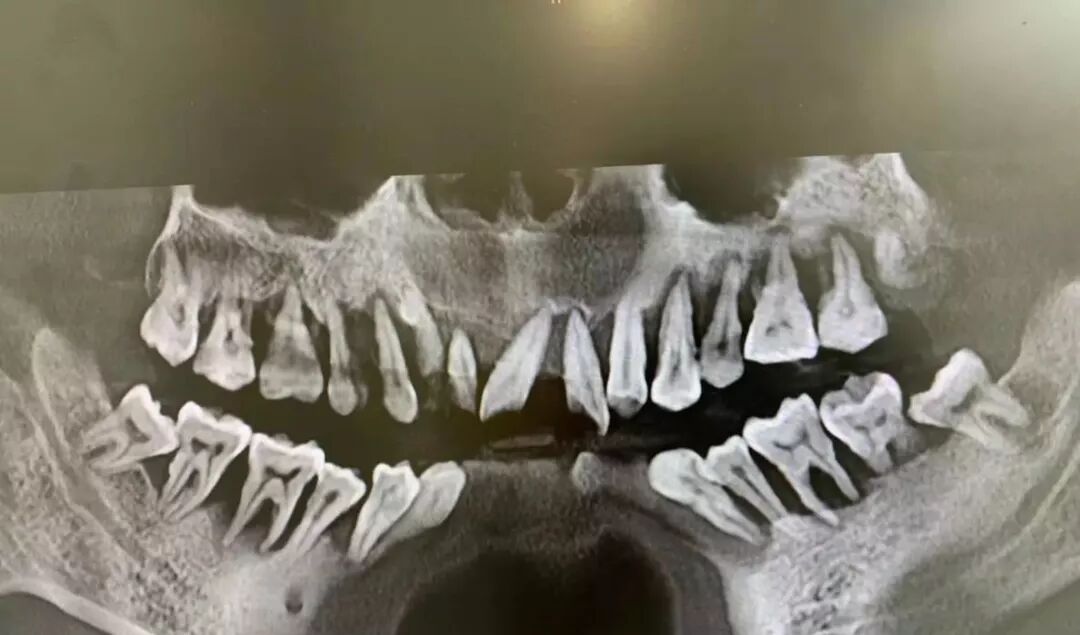

牙周炎不治疗,到最后就是这样的结果太可怕了

牙周炎到最后就是这样的结果太可怕了

可是一旦没有清洁掉他们,牙菌斑就会和口腔内的钙离子结合,形成牙结石,牙结石可是刷牙刷不掉的,它会源源不断的产生细菌以及毒素侵害牙周组织,导致牙龈红肿出血、牙槽骨(牙根周围的骨头)吸收,牙根暴露,最终牙齿松动、脱落。

牙周炎中重度后会出现牙齿松动,进而出现咬合无力、疼痛、影响咀嚼;也会出现牙缝变大、伸长移位而影响美观。此时再不就诊,后果就是牙齿脱落!